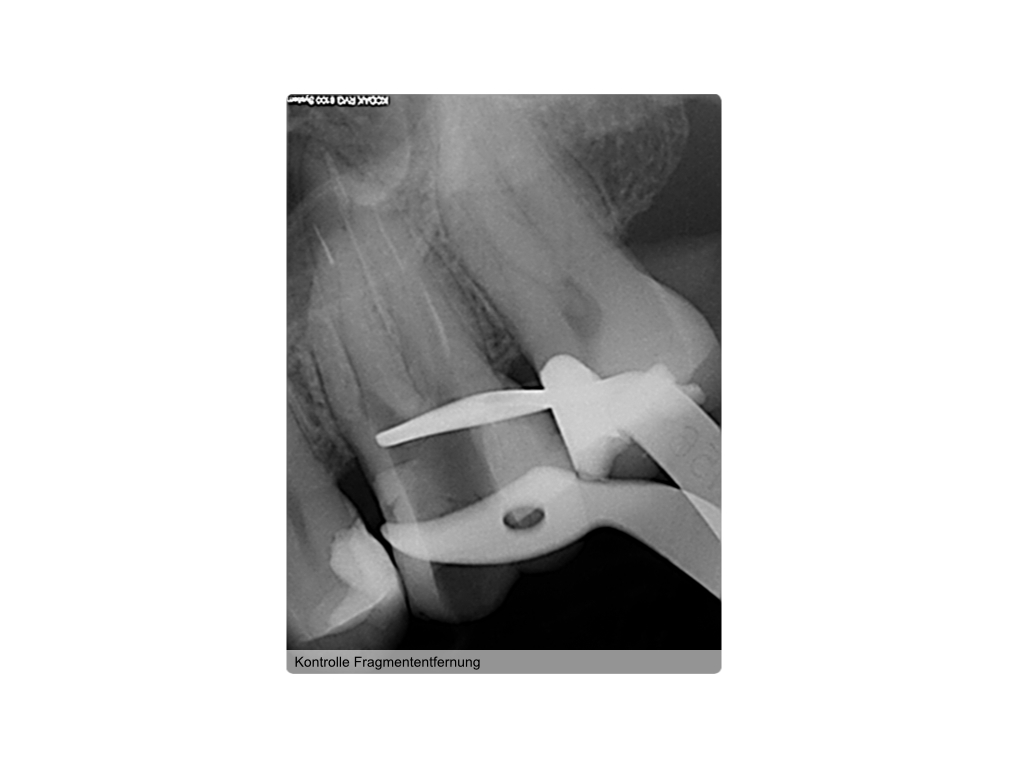

Instrumentenfraktur (3a)